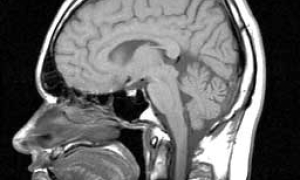

L’arrivée du numérique dans notre quotidien a révolutionné toutes nos pratiques et relations sociales. Cette technologie s’est développée à une vitesse fulgurante et est aujourd’hui indispensable. Retour en coulisses : Comment ça marche ? Quels sont ses avantages et inconvénients ? Les scientifiques bretons nous répondent. Nous retiendrons que ce qui peut être nocif, ce sont nos usages.